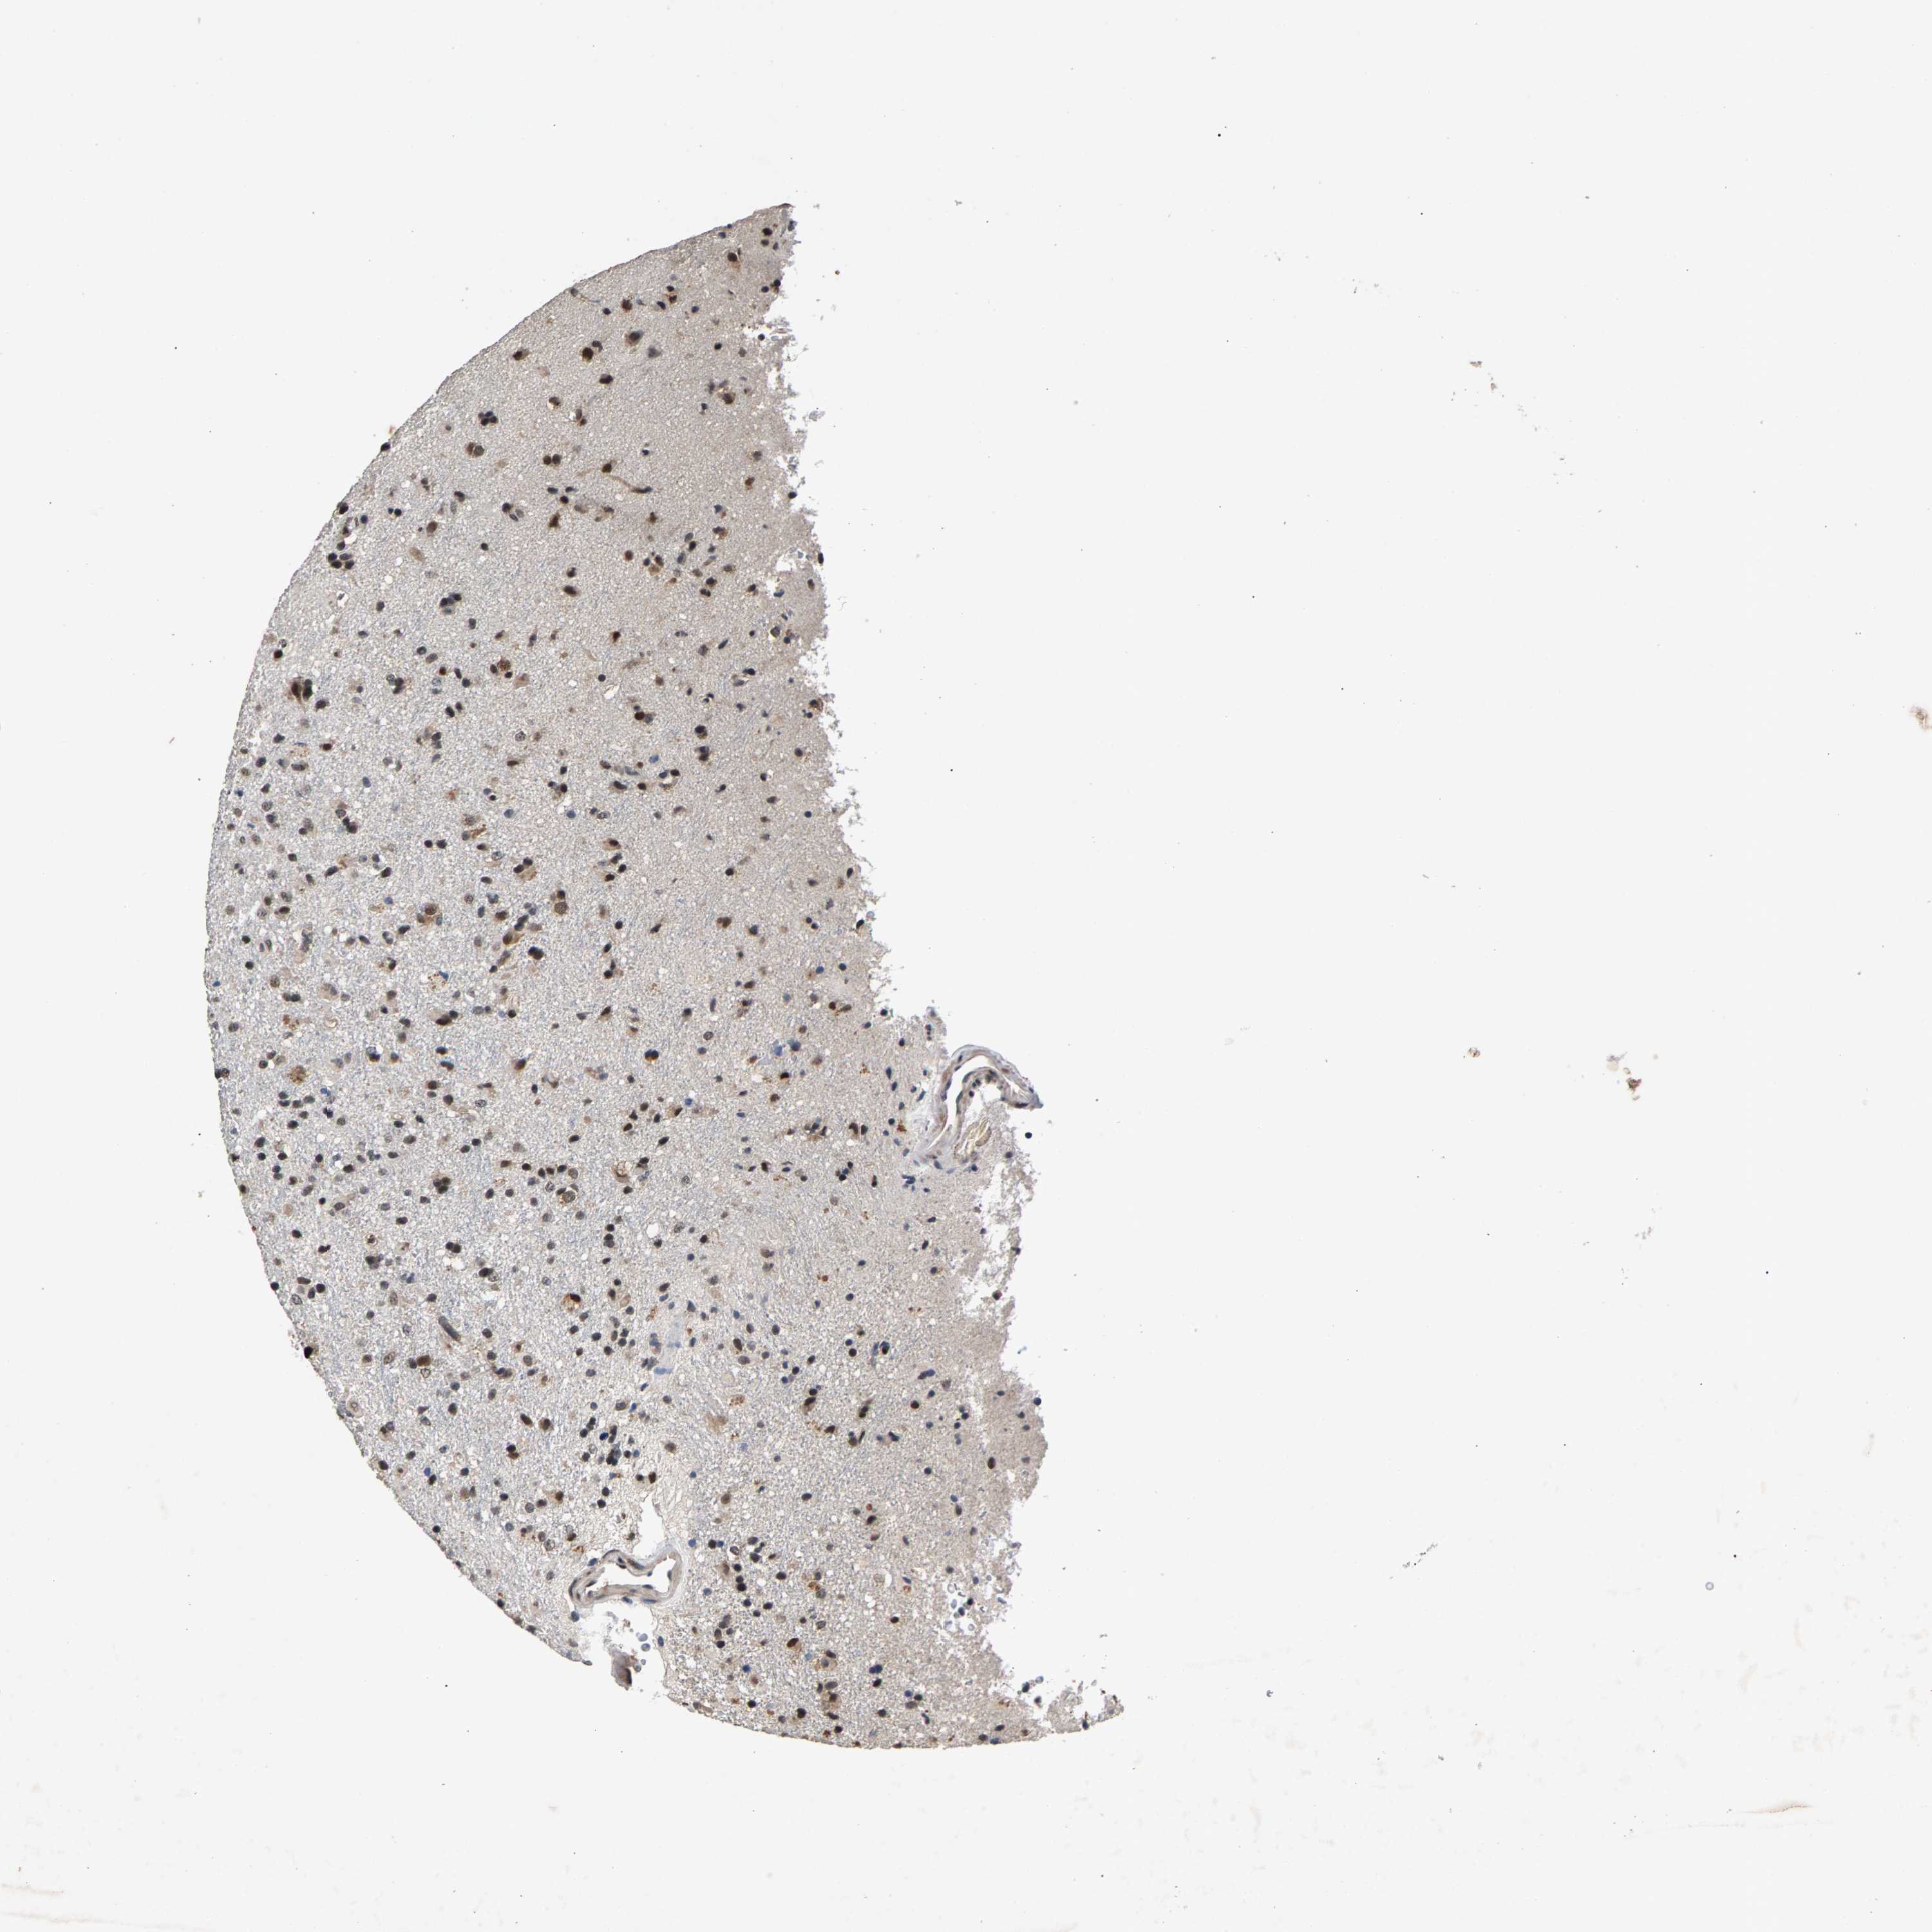

GLIOMA - Protein expressioni

A mouse-over function shows sample information and annotation data. Click on an image to view it in a full screen mode. Samples can be filtered based on level of antibody staining by selecting one or several of the following categories: high, medium, low and not detected. The assay and annotation is described here.

Note that samples used for immunohistochemistry by the Human Protein Atlas do not correspond to samples in the TCGA dataset.

Antibody stainingi

Antibody staining in the annotated cell types in the current human tissue is reported as not detected, low, medium, or high, based on conventional immunohistochemistry profiling in selected tissues. This score is based on the combination of the staining intensity and fraction of stained cells.

Each image is clickable and will lead to virtual microscopy that enables deeper exploration of all samples and also displays staining intensity scores, fraction scores and subcellular localization as well as patient and tissue information for each sample.

Antibody HPA019232

Antibody HPA021497

Antibody HPA021768

Staining

High

Medium

Low

Not detected

Intensity

Strong

Moderate

Weak

Negative

Quantity

>75%

75%-25%

<25%

None

Glioma, malignant, High grade

Glioma, malignant, Low grade